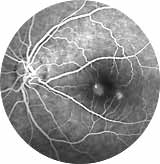

Fluoreszenzangiogramm: die krankhafte weiße Gefäss-Veränderung ist auf dem Bild oben nicht sichtbar

Was ist eine Fluoreszenzangiographie (FLA)? Die Fluoreszein-Angiographie (“Gefäßdarstellung”) dient dazu, Veränderungen am Augenhintergrund und dort insbesondere an den Blutgefäßen festzustellen. Viele dieser Veränderungen sind auch unter dem Mikroskop nicht ausreichend gut zusehen, so dass erst die Angiographie-Bilder Sicherheit in der Diagnosestellung und Therapie geben. (Wie beim Eisberg verbirgt sich häufig der größte Brocken unsichtbar in der Tiefe)

Was passiert bei der Untersuchung? Diese Untersuchung ist bis auf die Anwendung einer Venenverweilkanüle (wie beim Blutabnehmen) völlig schmerzfrei und besteht im Wesentlichen aus einer besonderen Form einer Augenhintergrundsfotografie. Für ein gutes Ergebnis der Untersuchung wird eine sehr gute Pupillenerweiterung benötigt – das kann häufig längere Zeit beanspruchen als für eine schon gewohnte Augenhintergrund - Untersuchung bei Ihrem Augenarzt. Bitte richten Sie sich, aufgrund der aufwändigen Untersuchung, auf eine Aufenthaltsdauer in unserer Praxis von ca. 2 Stunden ein. Ihnen wird während der Untersuchung ein wässriges Fluoreszenzmittel in die Armvene gespritzt, das mit einer Spezialkamera Undichtigkeiten im Blutgefäßsystem aufdeckt. Vergleichen Sie es mit einem Fahrradfahrer der einen „Platten“ hat und das unsichtbare Loch in seinem Schlauch finden will: ohne die Zuhilfenahme eines Eimer Wasser, in den er den Schlauch hält, sieht er die Luft nicht entweichen, die ihm das Leck zeigt.